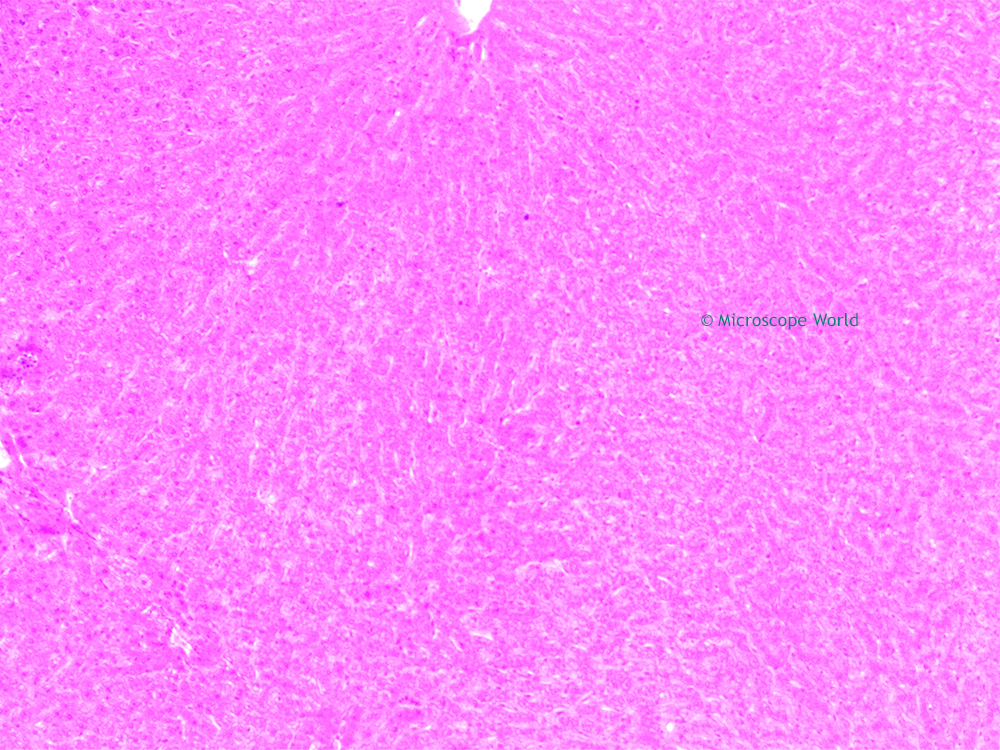

From blog.microscopeworld.com

Microscope World Blog Liver Under the Microscope Filter Blood Through Pig the experimental approach, called extracorporeal perfusion, involved circulating the patient’s blood through a. The achievement offers a potential temporary. The experiment is a step. a genetically modified pig liver successfully filtered the blood of a human who had completely lost brain activity and did so for three days. Filter Blood Through Pig.